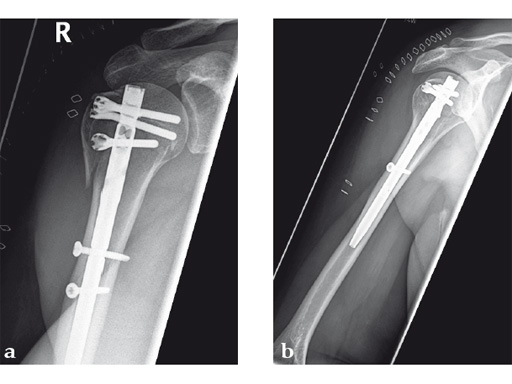

Case 2: Three-part valgus displaced fracture of the proximal humerus in a 63-year-old man.

The tuberosities have been reduced and fixed using intertubercular sutures (Fig 4). To reconstruct the medial support a calcar screw has been used. This determines the height of the nail. Therefore a 1 cm end cap has been used to get support for the proximal end of the nail in the part of the bone with the best bone quality.